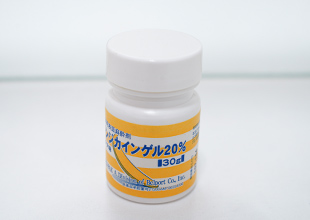

表面麻酔

麻酔針を刺す部分に塗布して、一時的に表面の感覚を麻痺させることで痛みを感じにくくします。

表面麻酔